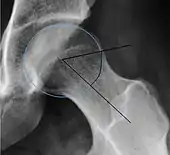

| Femoral head-neck offset | ![]() |

Offset of the femoral head with regard to most prominent aspect of the femora neck | >10 mm |

| Offset percentage | Femoral head-neck offset related to femoral head diameter | >0.18

| |